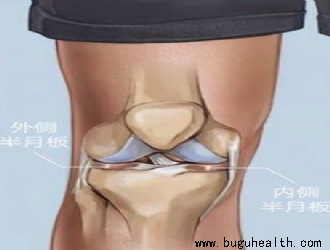

- ����ҽѧ���գ�ϥ�ؽڰ��°��������е���Ҫ�ԣ� BuGuRMC���ǿ���ҽ�����ģ���������ʦţҫ�� ��2023-01-31

- ϥϥ�ؽ�������������Ҫ�ij��عؽڣ�������վ�������к��˶�ʱ��ϥ�ؽھ�����������Ҫ�����á���ôϥ�ؽ�������ܹ��е�����������أ���͵�˵��ϥ�ؽ���һ����Ҫ����֯�������°塣����˼�壬���°�����Ӿ������£����Ը��ɹ���������ܺõ����ϣ�������ƽ�棬�������ֹ�ƽ̨�ϡ���һ��������Ϊ�ڲ���°��������.....